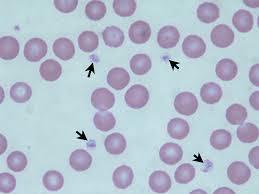

leukocytes

Plasma

Platelets